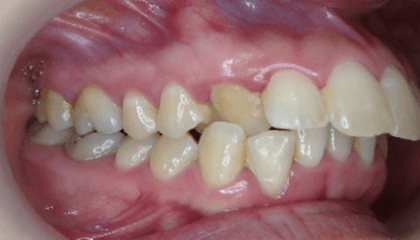

治療前

特に前歯が噛んでいない状態と八重歯は奥歯に負担がかかり、むし歯や歯周病が進行しやすい噛み合わせです。

下の前歯が、先天的に1本少ない患者さんです。上下の歯の本数が違うために、右上犬歯が八重歯になっています。